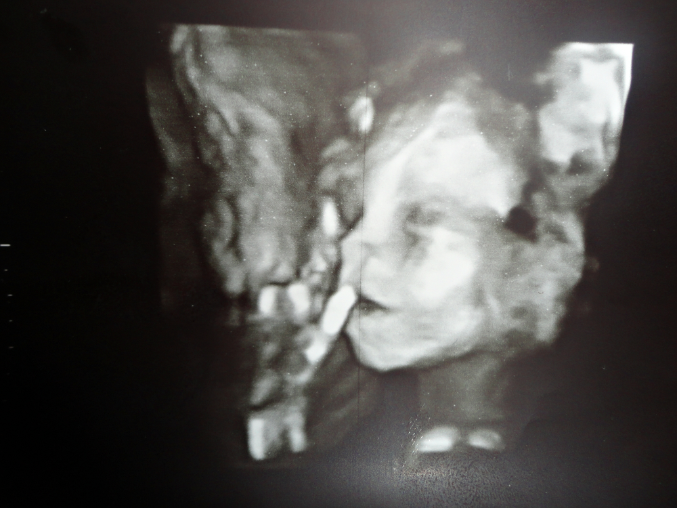

УРАААААААА!!!))))Девочка!)))

Сегодня сходила на УЗИ, все у нас (тьфу-тьфу) хорошо) мы крупненькие, поэтому и животик такой большой) Я очень рада, что у меня будет доченька! Илона, мама тебя очень любит и ждет!